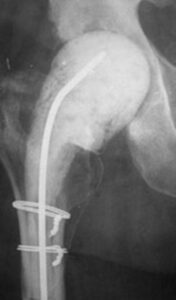

Total knee and hip replacements are among the most commonly performed elective surgeries, significantly improving the quality of life for many patients by relieving pain and enabling them to engage in more active lifestyles.

However, joint replacements, which are made of metal and plastic, present a unique challenge for the immune system. Metal surfaces attract bacteria, and since these implants do not receive blood flow, the immune system has difficulty detecting and responding to bacterial presence around them. As a result, bacteria may colonize the metal implants, multiply, and lead to an infection in the joint.